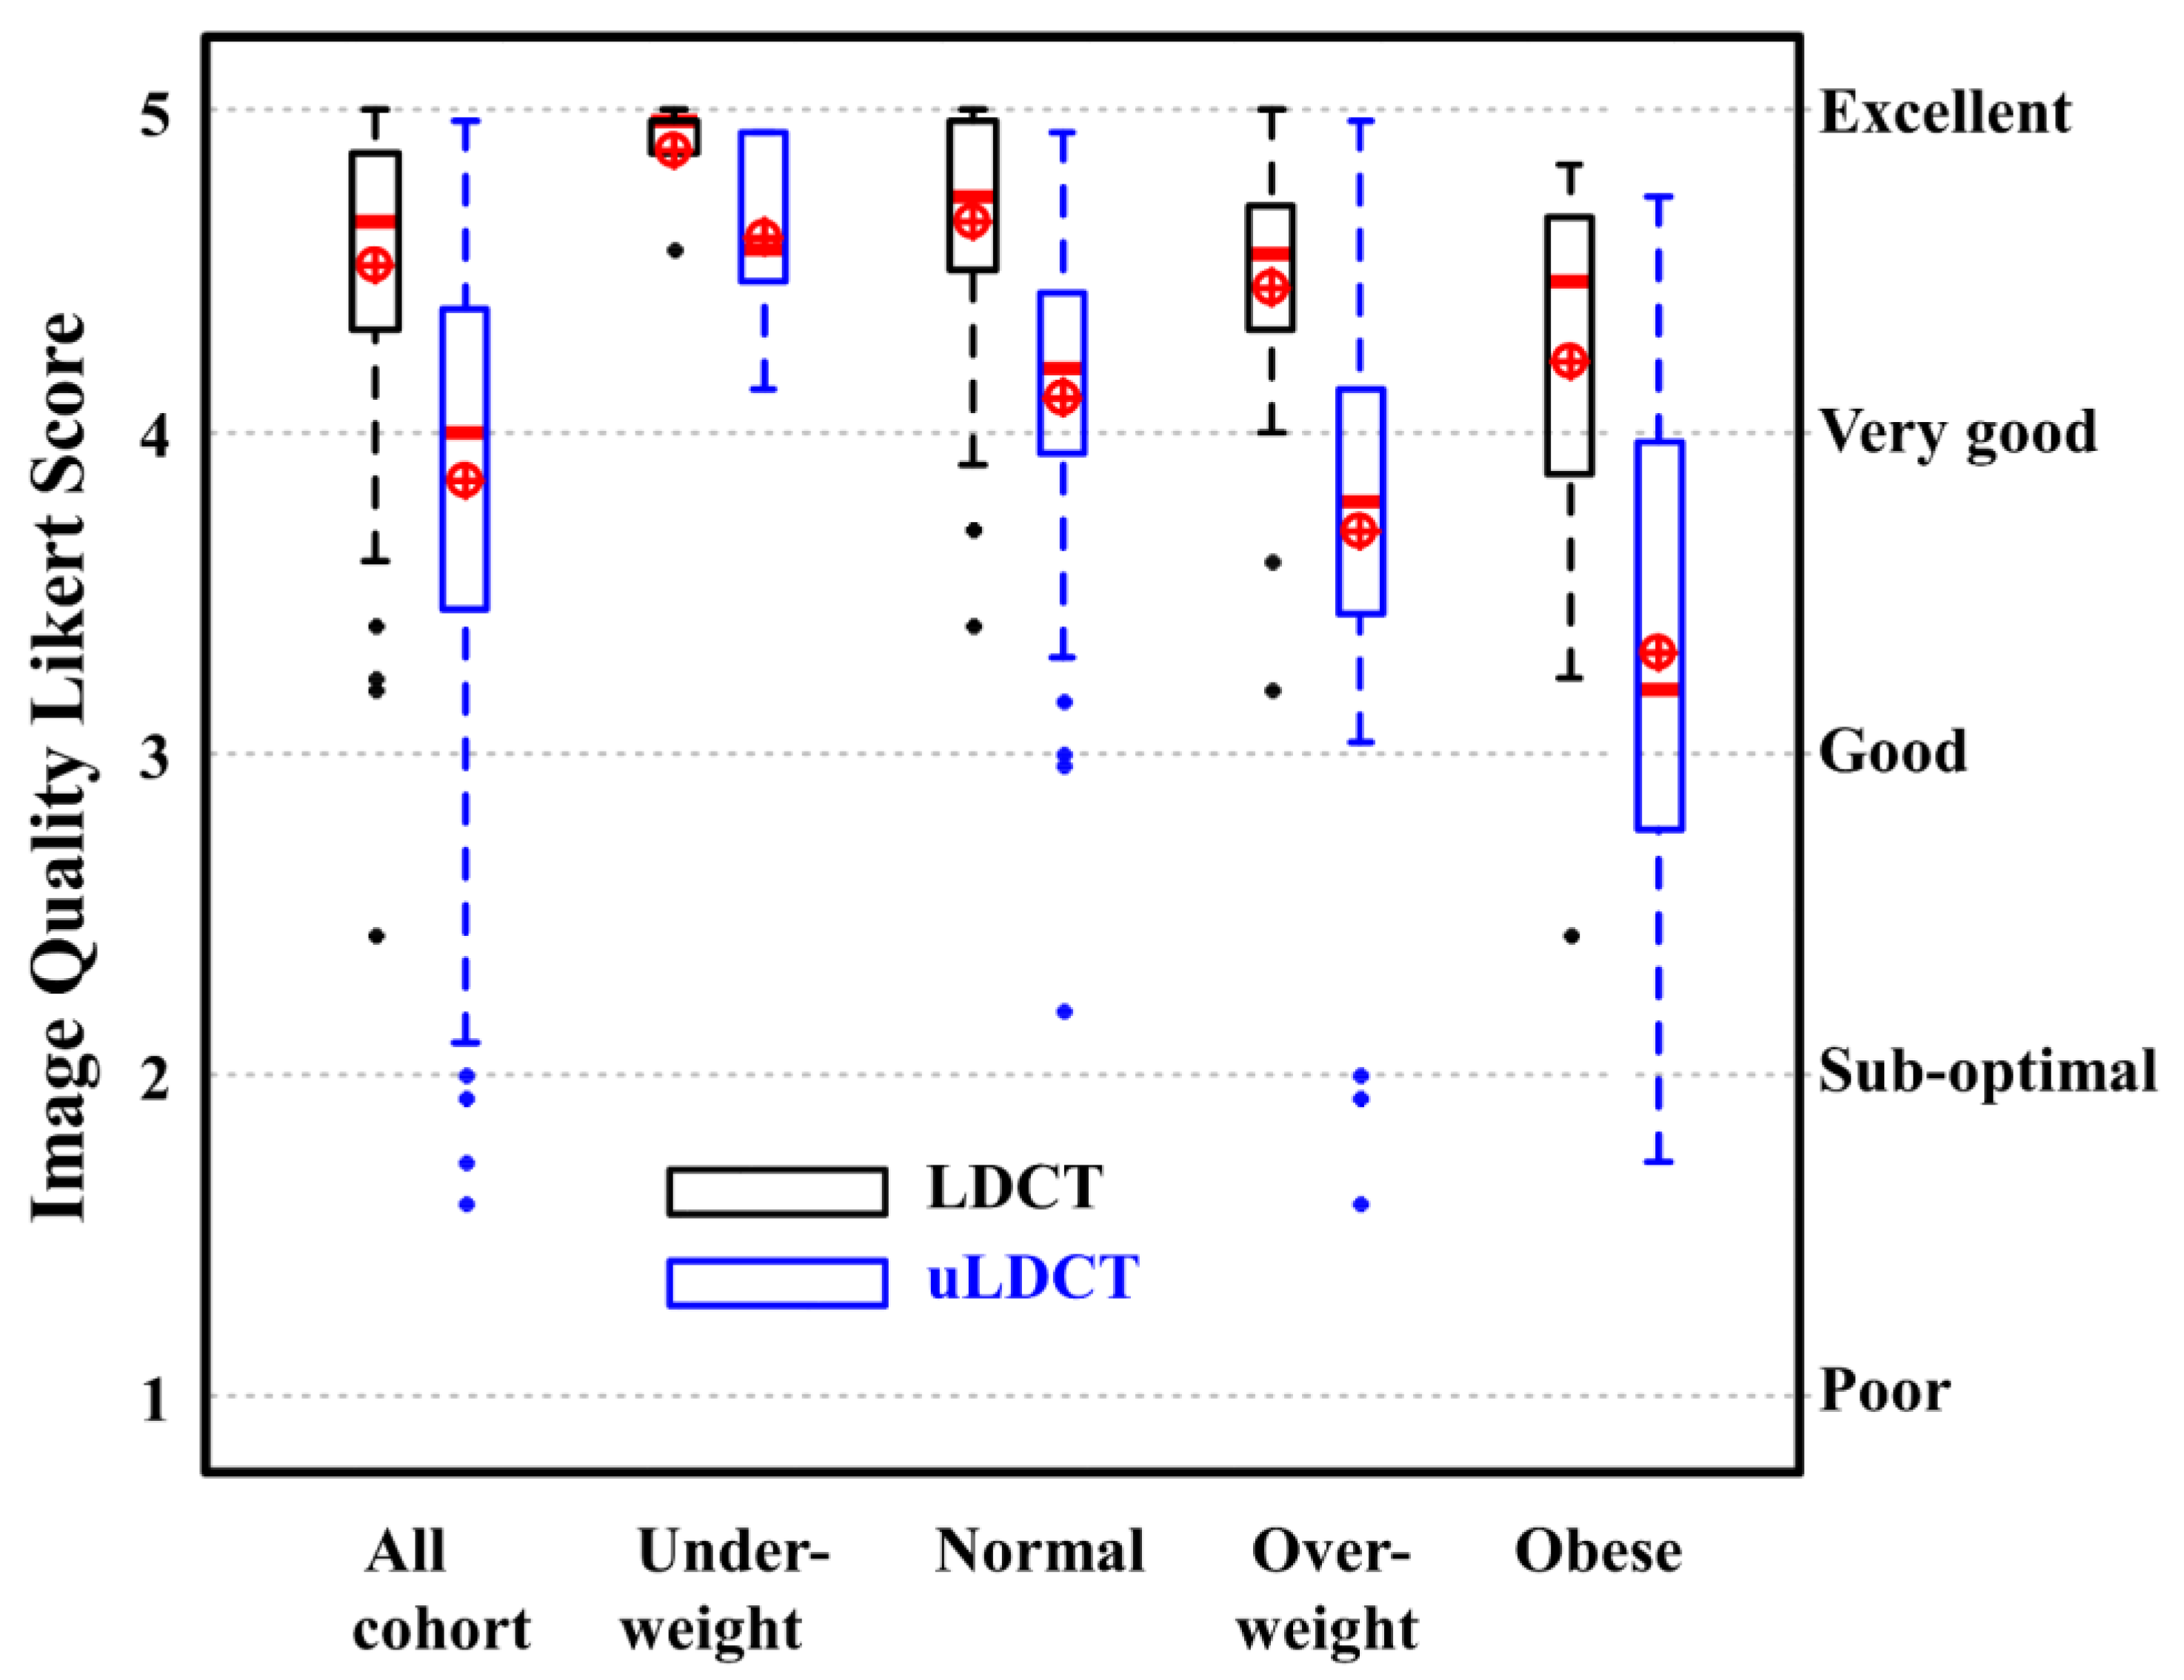

4.1. Image Quality (IQ) Assessment

4.2. Diagnostic Confidence Assessment